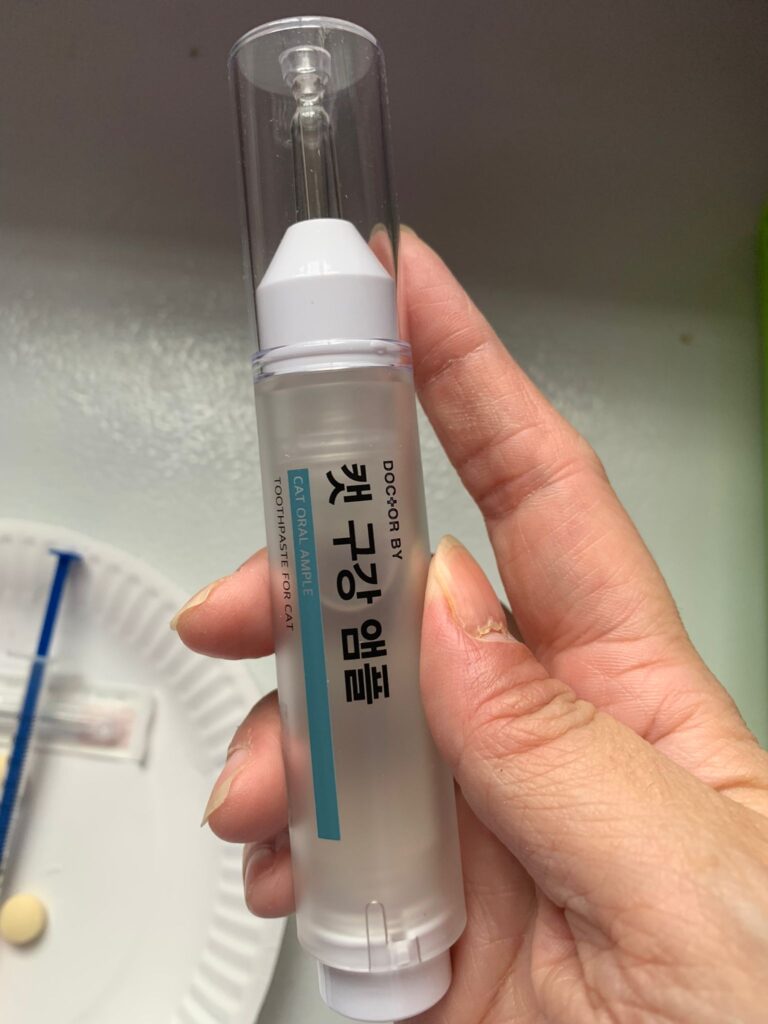

Morning: given doctorby toothpaste – he ok.

Morning: given him doctorby oral and bupre